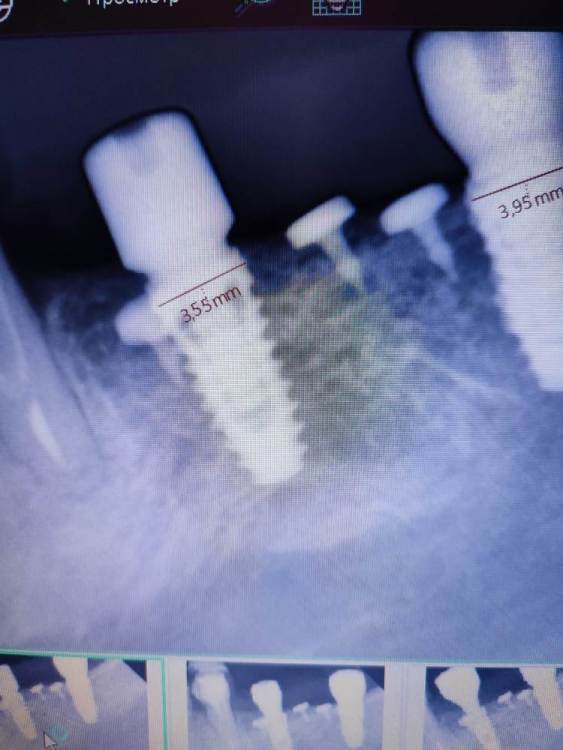

АнтонТЛТ Опубликовано 22 октября, 2022 Поделиться Опубликовано 22 октября, 2022 11 минут назад, kriokov сказал: не смог нормально поставить ФДМ на необиотек 3. 5 и 4.0. ФДМ от дентиума. Кость не мешала, убирал римерами. Шахта чистая. Какая причина может быть? Снимок не делали? Ссылка на комментарий

kriokov Опубликовано 22 октября, 2022 Поделиться Опубликовано 22 октября, 2022 6.5 , только на такую глубину, далее 5.5 тоже не сел, потом от мис поставил, . По снимкам кажется что кость . На самом деле полно места. Не пойму, что не так сделал. Ссылка на комментарий

АнтонТЛТ Опубликовано 22 октября, 2022 Поделиться Опубликовано 22 октября, 2022 42 минуты назад, kriokov сказал: Точно. Еще был под рукой от осстема, я не стал пробовать . От миса сел . К следующему пиему привезут родные. отпишусь. Не понятно почему один и тот же фдм в один болт вошел а в дугой нет. Может быть конусность чуть разная или это домыслы? Домыслы. Может с резьбой что-то у фдм. По рентгену же видно, что до конуса не дошло. 1 Ссылка на комментарий